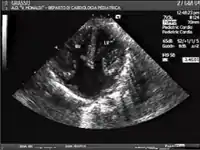

Ultrasound showing a complete atrioventricular septal defect

AVSDs can be detected by cardiac auscultation; they cause atypical murmurs and loud heart tones. Confirmation of findings from cardiac auscultation can be obtained with a cardiac ultrasound (echocardiography - less invasive) and cardiac catheterization (more invasive).